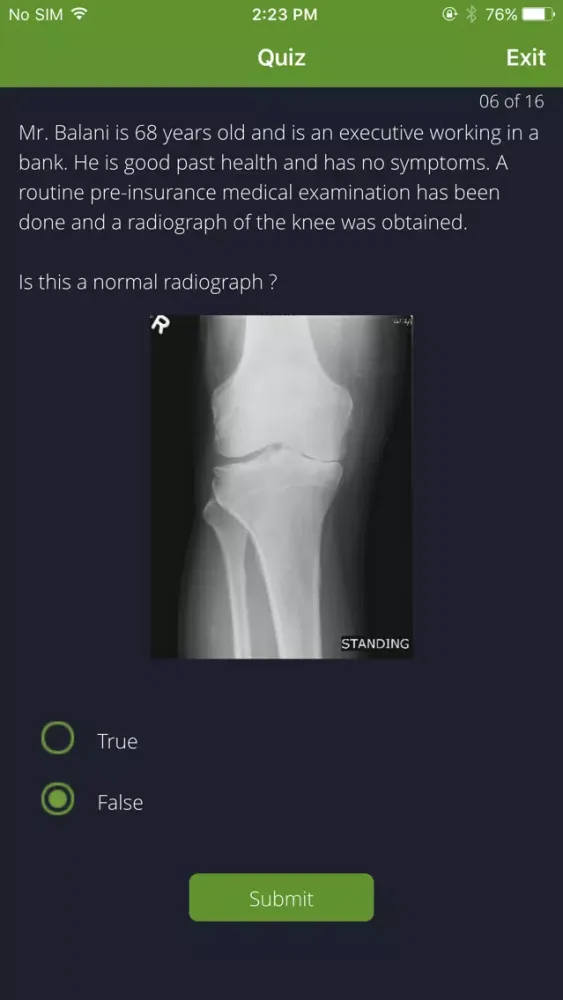

- A quiz designed to test your knowledge of musculoskeletal medicine and introduce you to basic film interpretation skills. A 'hint' dialogue box appears after submitting an answer, encouraging you to re-evaluate your interpretation.

- Review clinical situations on the basis of case examples in a format similar to that of clinical vignettes.